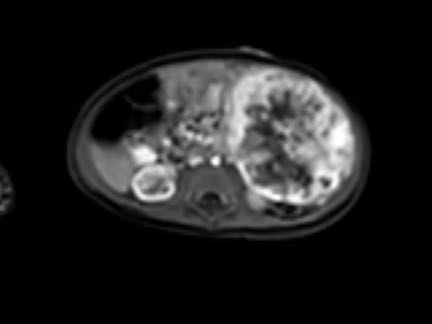

Mức độ lan rộng của khối u được đánh giá rõ ràng trên chuỗi xung TSE T2 weighted 3D theo mặt phẳng axial.

The left kidney is compressed and displaced caudally.

Có di căn hạch bạch huyết cạnh động mạch chủ (mũi tên vàng nhỏ).

Nguyên ủy của thân tạng và động mạch mạc treo tràng trên bị khối u bao quanh (đầu mũi tên).

Tĩnh mạch chủ dưới bị đẩy ra phía trước (mũi tên xanh).

Xẹp phổi hai bên ở vùng lưng thường được thấy trên MRI, vì việc kiểm tra được thực hiện dưới gây mê.